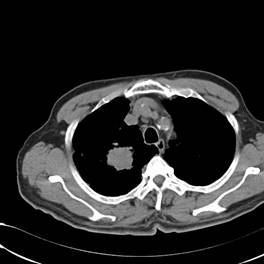

典型病例2:患者张XX,男,65岁,住院号:496686,因发热、胸闷、背痛2月余入院,体温最高达39℃,背部疼痛难忍。2015年6月29日胸部增强CT示:右肺下叶11.6cmx12.5cm巨大肿块,中心大片低密度坏死区,第8胸椎及右侧第8后肋骨转移。于7月2日行CT引导下穿刺活检术,病理证实为右肺鳞癌。给予125I放射性粒子植入治疗,术中首先利用植入针,穿刺肿块中央坏死区,连接引流袋后抽出肿瘤内坏死液体约500ml,抽液后肿瘤缩小约1/3;随后将125I粒子植入到第8胸椎体及第8后肋骨转移区,同时重点放置患侧滋养动脉供血区域。术后第二天,患者体温恢复正常;术后一周随访,患者背痛缓解。该患者出院回家,仍在随访中。

术前CT片